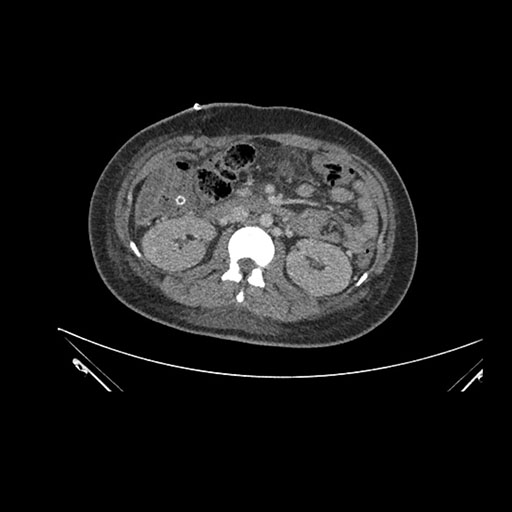

Imaging Analysis

Look through the patient's CT scan to identify any areas of concern for the necessary procedure.

Axial Arterial

Based on initial findings, which issue(s) would you be most concerned about?